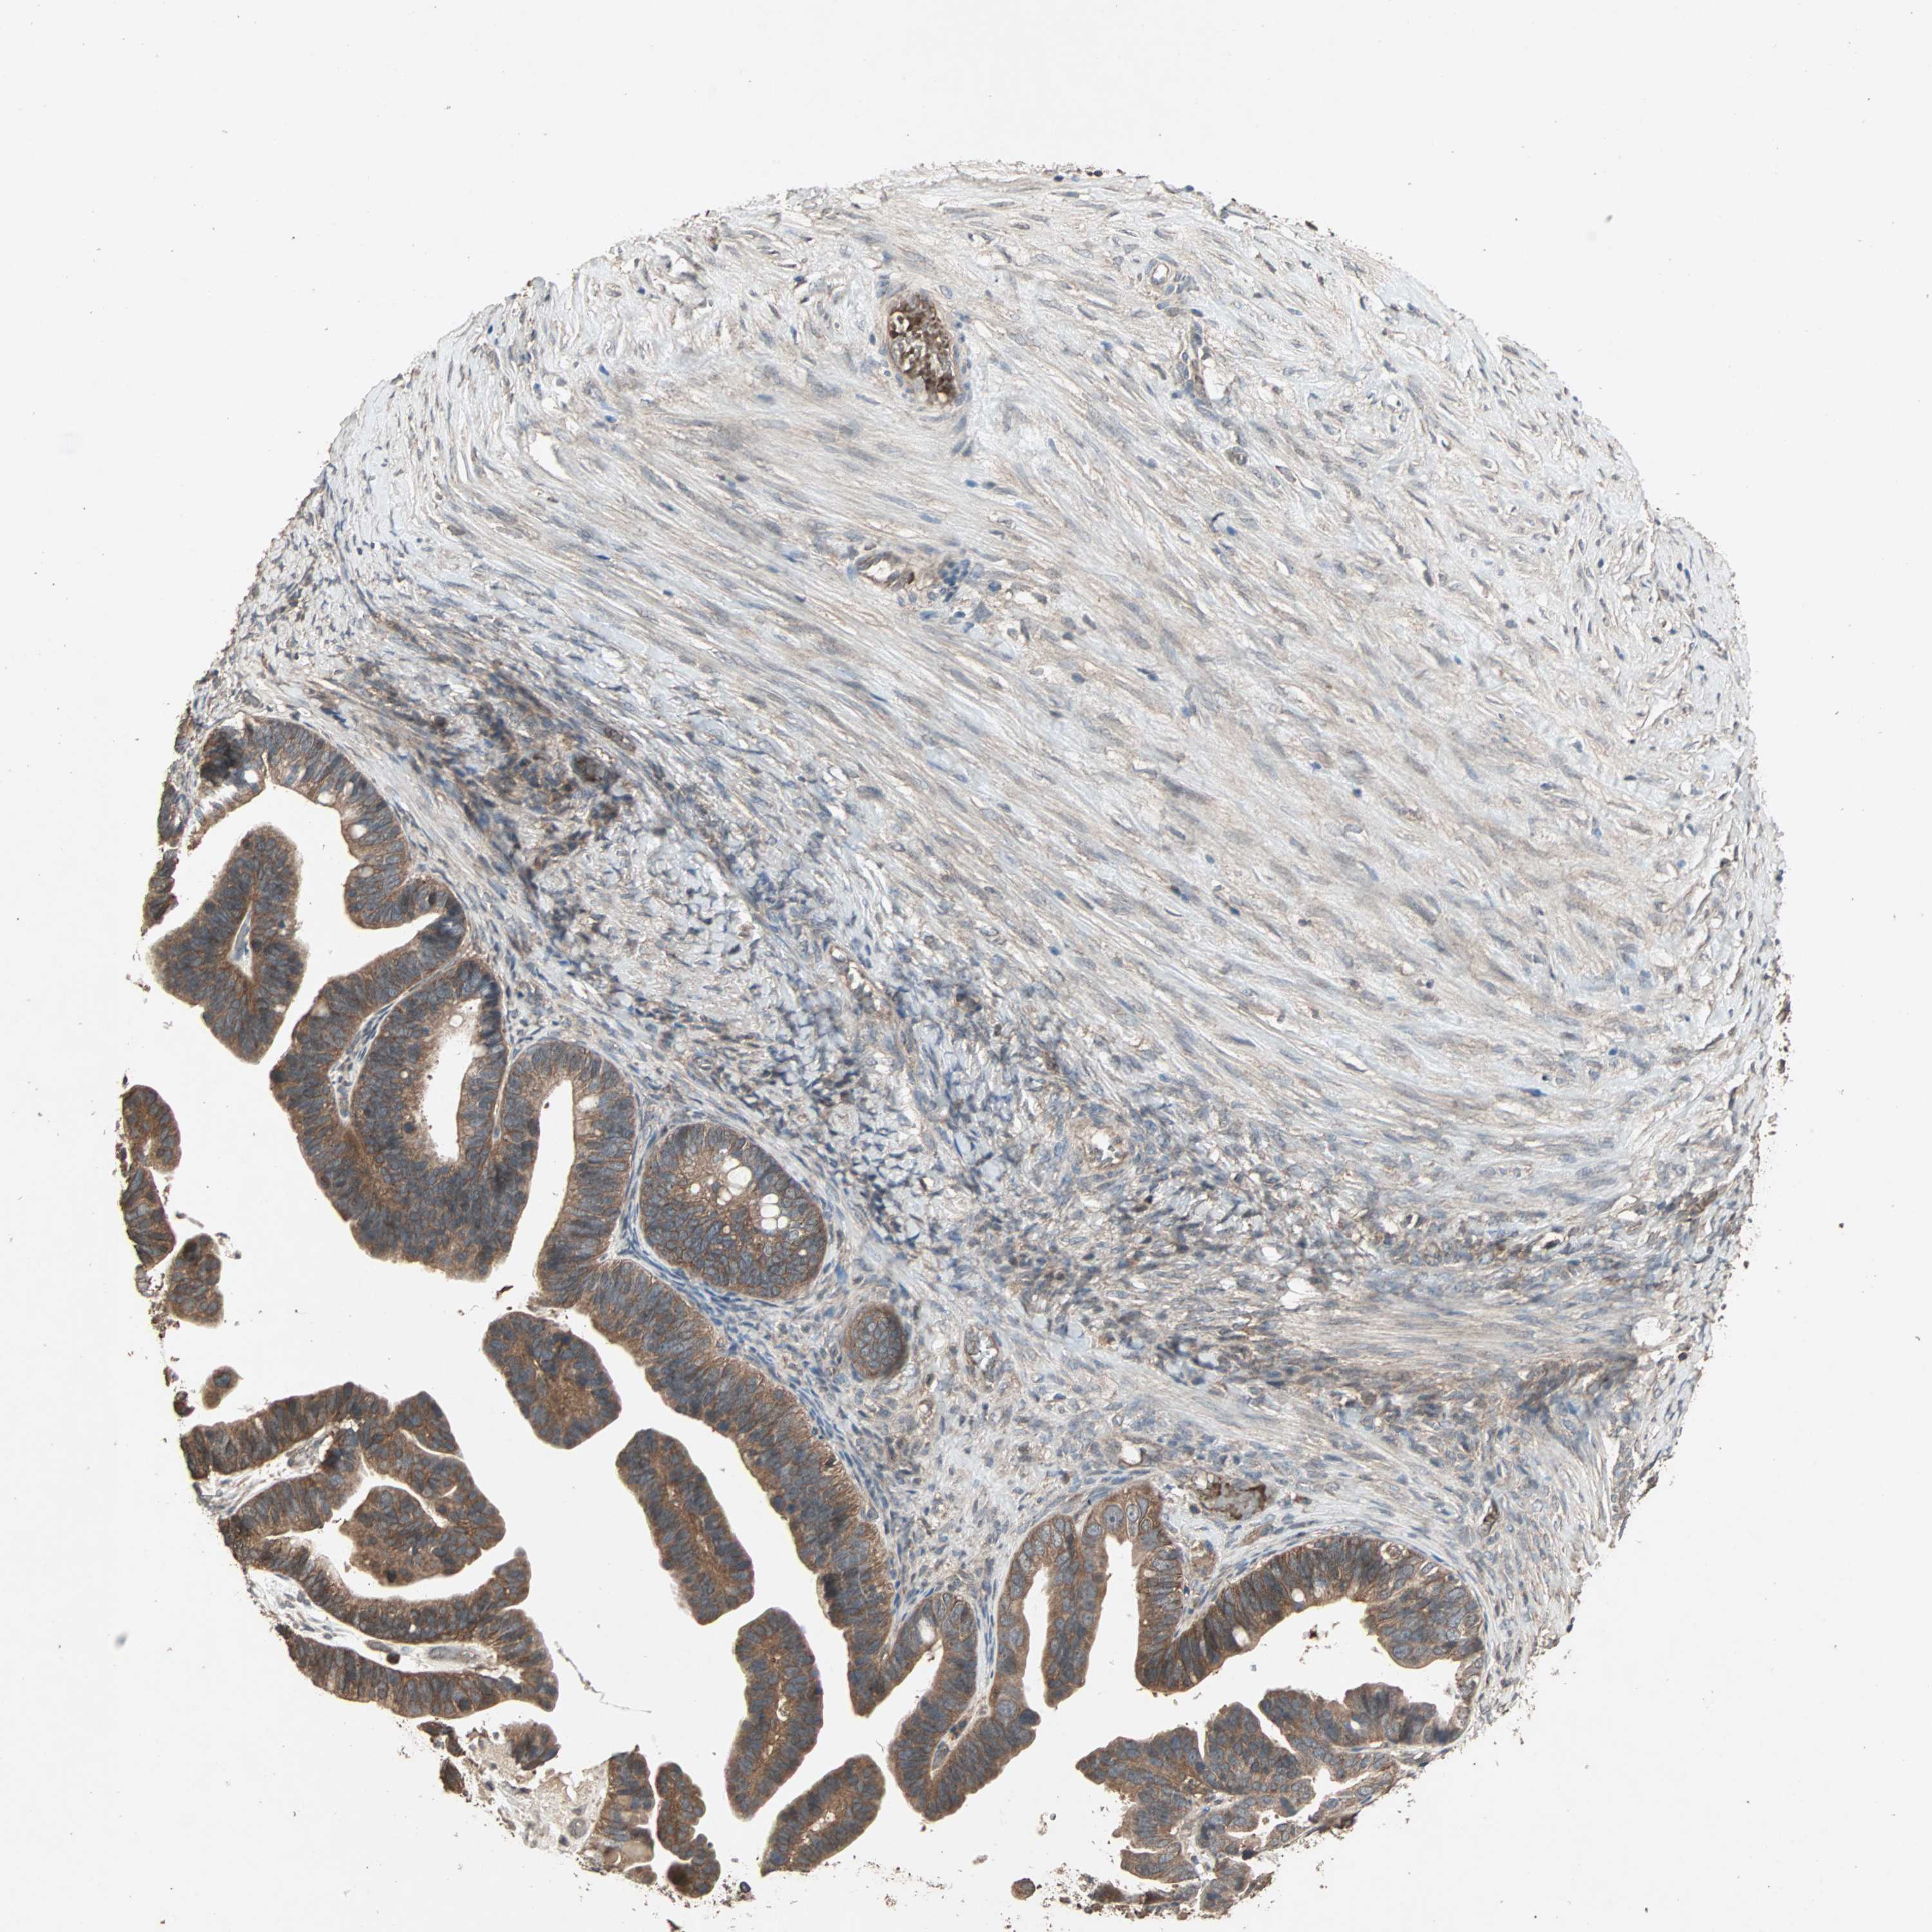

OVARIAN CANCER - Protein expressioni

A mouse-over function shows sample information and annotation data. Click on an image to view it in a full screen mode. Samples can be filtered based on level of antibody staining by selecting one or several of the following categories: high, medium, low and not detected. The assay and annotation is described here.

Note that samples used for immunohistochemistry by the Human Protein Atlas do not correspond to samples in the TCGA dataset.

Antibody stainingi

Antibody staining in the annotated cell types in the current human tissue is reported as not detected, low, medium, or high, based on conventional immunohistochemistry profiling in selected tissues. This score is based on the combination of the staining intensity and fraction of stained cells.

Each image is clickable and will lead to virtual microscopy that enables deeper exploration of all samples and also displays staining intensity scores, fraction scores and subcellular localization as well as patient and tissue information for each sample.

Antibody HPA005651

Staining

High

Medium

Low

Not detected

Intensity

Strong

Moderate

Weak

Negative

Quantity

>75%

75%-25%

<25%

None

Location

Nuclear

Cytoplasmic/membranous

Cytoplasmic/membranous,nuclear

Cystadenocarcinoma, serous, NOS

Carcinoma, endometroid

Cystadenocarcinoma, mucinous, NOS

Carcinoma, NOS